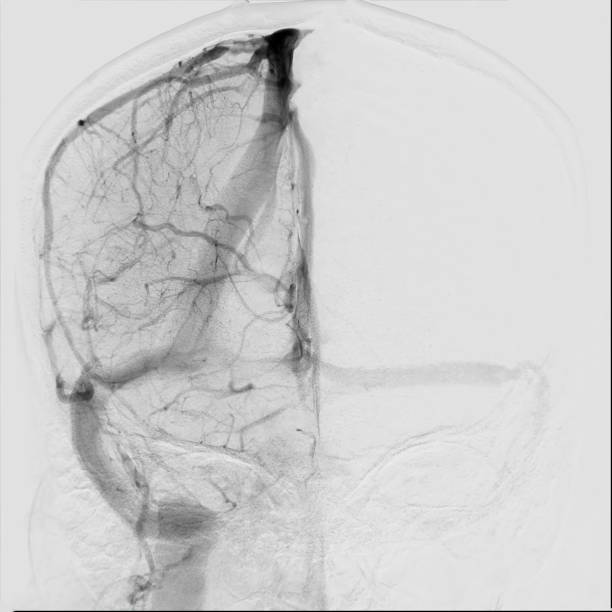

🟢 뇌경색이란 무엇인가요?

뇌경색은 뇌혈관이 막히면서 해당 부위에 혈액이 공급되지 않아 뇌세포가 손상되는 질환이에요.

**‘허혈성 뇌졸중’**이라고도 하며, 전체 뇌졸중의 약 **70~80%**를 차지할 만큼 흔한 형태입니다.